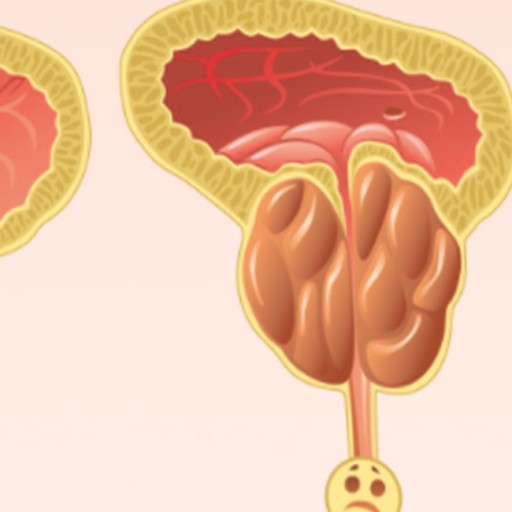

남자의 건강을 위협하는 대표 질병 중 한 가지는 전립선 질병이다. 전립선염은 남자의 50%가 일생에 한 번은 겪어볼 정도로 흔한 질병이 됐으며, 전립선암은 최근 20년간 20배 넘게 증가할 정도로 대중적인 질환이 되었는데요.

전립선에 좋은 음식 전립선에 유익한 음식 15가지를 소개해드릴 텐데요. 지금부터 소개해드릴 음식만 잘 챙겨드시면 전립선 건강에 큰 도움이 되지 않을까 생각되니 꼭 의심해 보시길 권한다.